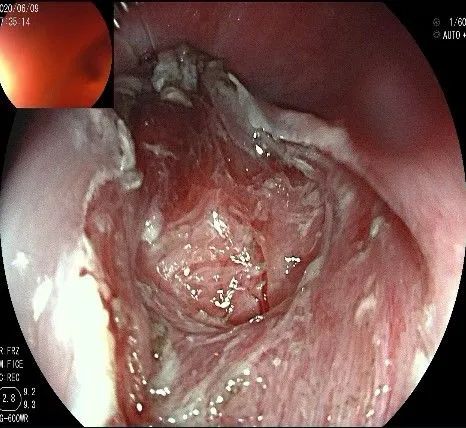

瘤子切除后,在粘膜切开的地方,固有肌层的纵形肌处形成一个开口。

倒镜观察,隆起已经消失。

夹闭创面的时候做胃镜吸引,利于创面闭合。

创面夹闭完成,反复冲洗观察,无出血及穿孔。结束手术,等待病理结果。